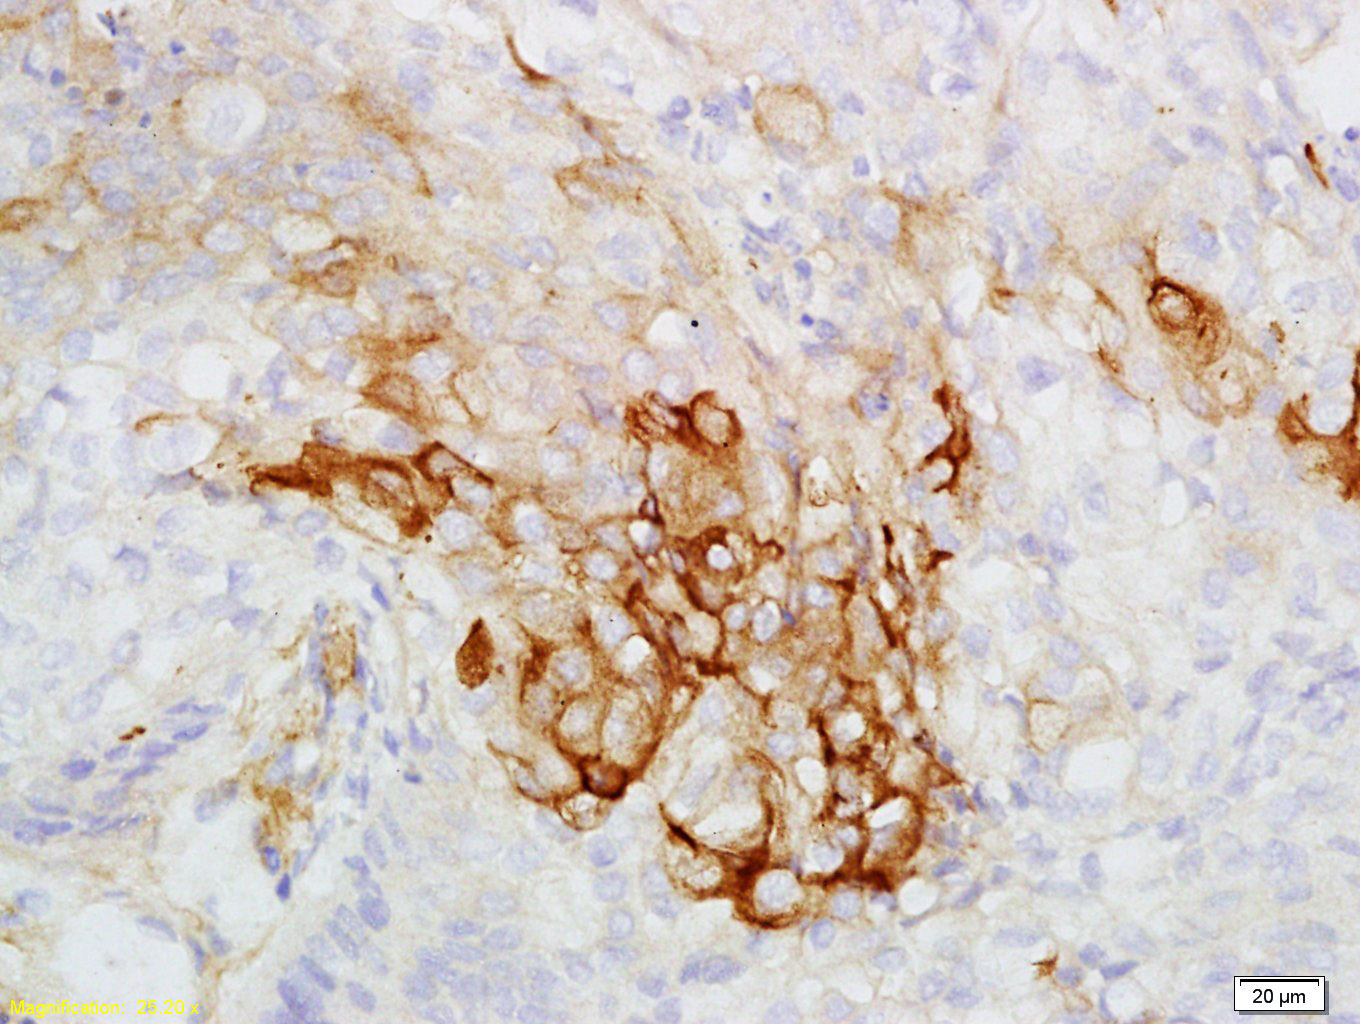

Tissue/cell: human laryngocarcinoma; 4% Paraformaldehyde-fixed and paraffin-embedded; Antigen retrieval: citrate buffer ( 0.01M, pH 6.0 ), Boiling bathing for 15min; Block endogenous peroxidase by 3% Hydrogen peroxide for 30min; Blocking buffer (normal goat serum,C-0005) at 37℃ for 20 min; Incubation: Anti-CK7 Polyclonal Antibody, Unconjugated(bs-1610R) 1:200, overnight at 4°C, followed by conjugation to the secondary antibody(SP-0023) and DAB(C-0010) staining